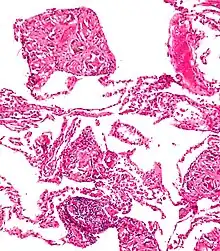

| An endoscopy image of the stomach, showing a foreign body in the form of a toothbrush. | |